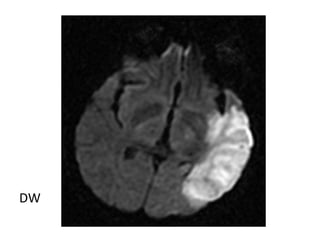

1-Diffusion Abnormality :

-Abnormalities may be seen within minutes of

arterial occlusion with diffusion-weighted MRI

-Standard diffusion protocol includes a DWI and an

apparent diffusion coefficient (ADC) image ,

these are usually interpreted side by side

-DWI : summation of diffusion and T2 effects ,

abnormalities appear as high signal

-ADC : diffusion effects only , abnormalities appear

as low signal

-Diffusion is the most sensitive modality , DWI

hyperintensity & ADC map hypointensity reflect

reduced diffusivity which can be seen within minutes

of the ictus

Acute Left MCA Infarct

T1

T2

DWI

ADC

RT MCA infarction , (A and B) Restricted water diffusion in the region

of infarct results in an increased signal intensity on diffusion (A) and

decreased signal on apparent diffusion coefficient imaging (B)